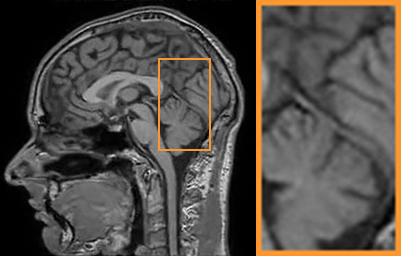

To demonstrate the robustness of our approach, we first apply it on various MRI data including the chest, cardiac and renal (?). In Tab. 2, Our proposed framework gives the highest PSNR for all of the tree types of MR images. Fig. 7 visualizes the corresponding results for chest data. we can see that our approach prevails over others in detail restoration at the junction of blood vessels as well as noise removal in the background. Actually, our method has a stronger ability to handle slight noise because of the subprocess of learning based optimization with deep prior. To demonstrate that, we add Rician noise at level of 20 to 25 T1-weighted MRI and 25 T2-weighted MRI to generate the noisy data. As what is shown in Fig. 8, our method over leads all the competitors by a large margin when the input is corrupted with Rician noise.

Benchmark: We then compare our method with other CS-MRI techniques on the task of CS-MRI with noise. The -weighted and -weighted MRI data in IXI dataset are adopted as test benchmark. Since the compared methods don’t have mechanism to handle Rician noise, we separately assign a classical Rician noise remover RicieOptVST and our learnable architecture for them to execute the denoising after CS reconstruction. As shows in Tab. 3, our CS-MRI framework has superiority against others based on both RicieOptVST and our network. Furthermore, the choice of taking our learnable architecture as the denoiser performs better than that of taking RiceOptVST and the last column shows that the proposed framework surpasses all the combinations. In Fig. 10, we can have a more intuitive understanding to the reconstruction comparison. More details are preserved in our framework than competitive approaches.